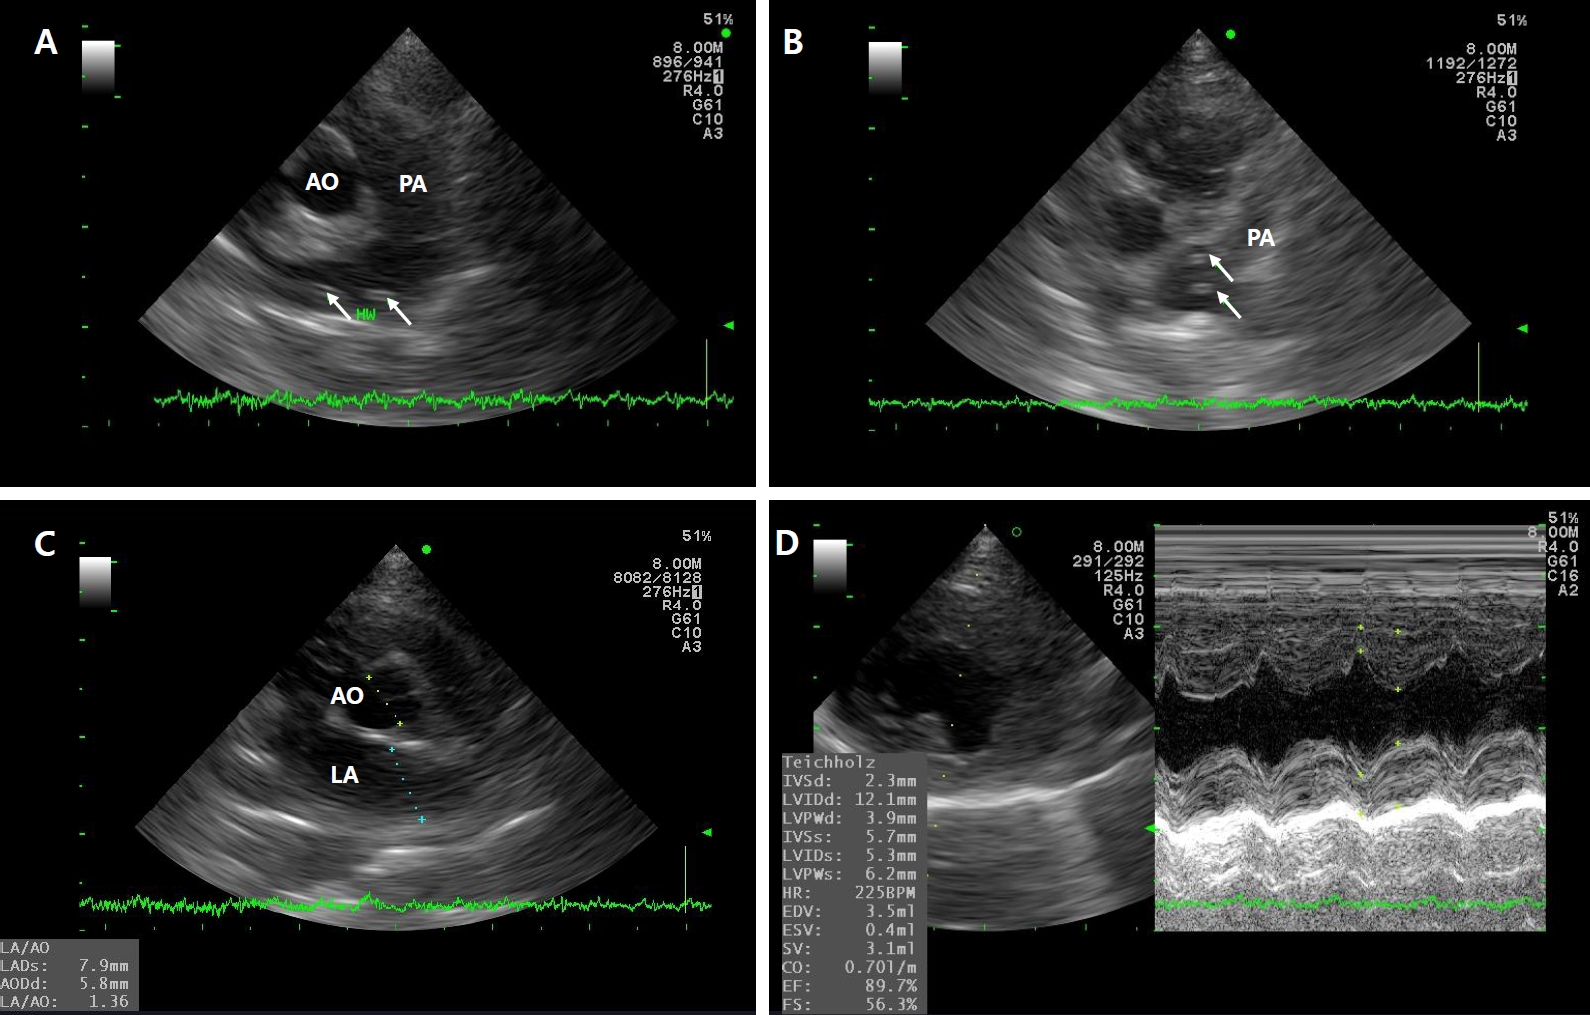

The cat was treated with oxygen supplementation, maintenance fluid therapy, prednisone [1 mg/kg orally (PO) twice daily (BID)], doxycycline (5 mg/kg PO BID), acetylcysteine (10 mg/kg PO BID), pheniramine (1 mg/kg PO BID), and metronidazole (10 mg/kg intravenously BID). Daily thoracic radiographs were obtained to monitor lung condition (

Fig. 1). On hospitalization day 5, thoracic radiographs showed normalization of pulmonary fields. At discharge, prednisone (1 mg/kg PO BID), doxycycline (5 mg/kg PO BID), acetylcysteine (10 mg/kg PO BID), and pheniramine (1 mg/kg PO BID) were prescribed for an additional week to manage HARD [

Fig. 1.Thoracic radiographs of Case 1. Day 1: (A) ventrodorsal view and (B) right lateral view. Pulmonary artery enlargement extending to the right caudal lung lobe is evident in the dorsoventral projection. Additionally, interstitial infiltration is present in the lung field, with multiple fissure lines observed. Day 5: (C) ventrodorsal view and (D) right lateral view. Compared with the findings on Day 1, pulmonary infiltration decreased over the 5-day period.